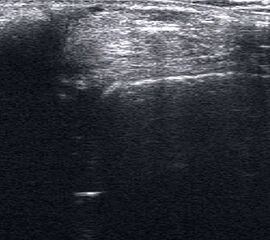

Ruptur Lig. fibulotalare anterius

Lagerung: Rückenlage, OSG in Plantarflexion.

Schnittebene: LS über Lig. talofibulare anterius.

Referenzstrukturen: Fibulakante und Talushals.

Befunde: Das Lig. talofibulare ant., verläuft (mit häufigen Anlagevarianten) beim Gesunden als meist dreieckige oder parallele echogene Struktur von der Fibula bis zur Spitze des im Schnitt pyramidenähnlichen Talus. Darunter ist ggf. Gelenkknorpel erkennbar (Abb. 15). Beim Erwachsenen reißt das Band meist distal ab und schlägt sich zum Talus hin ein (Abb. 16). Bei Kindern reißt das Band meist mit einer osteochondralen Schuppe fibular ab (Abb. 17). Zwischen Band und Knochen drängt oft echoarmes Hämatom nach außen, das im Dekompressionstest deutlicher darstellbar wird (Abb. 18). In derselben Untersuchungsposition kann die Stabilität schnell und weitgehend schmerzfrei überprüft werden (s. u.).